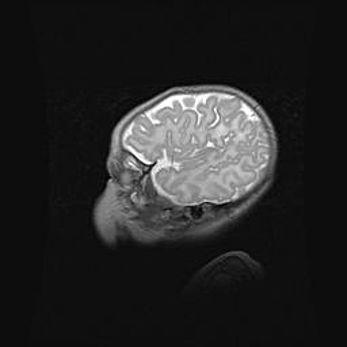

Лейкомаляция с кистозно-глиозной дегенерацией головного мозга.

Возраст: 2 месяца 25 дней

Вес: 6400 г

Окружность головы: 40 см

Срок гестации: 41 неделя

Лейкомаляцию относят к ишемически-гипоксическим повреждениям головного мозга, диагностируемым у новорожденных. При лейкомаляции в головном мозге обнаруживают очаги некроза, возникшие после тяжелой гипоксии и нарушения кровотока. В процессе морфогенеза очаги проходят три стадии: 1) развития некроза, 2) резорбции и 3) формирования глиозного рубца или кисты. Перивентрикулярная лейкомаляция (ПЛ) встречается примерно в 12% случаев среди новорожденных, обычно – у недоношенных детей, причем, частота ее зависит от массы, с которой младенец появился на свет. Наибольшее число малышей страдает лейкомаляцией, если масса при рождении 1500-2500 г.